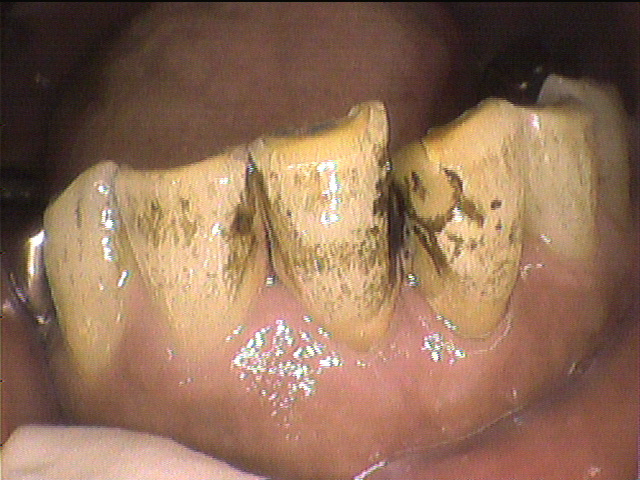

クリーニング前

数年ぶりにクリーニングにいらした患者さんです。

タバコやコーヒーによる着色、歯石、プラークがべったりと付着していました。

1回では取り切れないため、2回に分けてクリーニングを行うことになり

特に汚れが目立っていた下の前歯を中心に、できる限り除去しました。